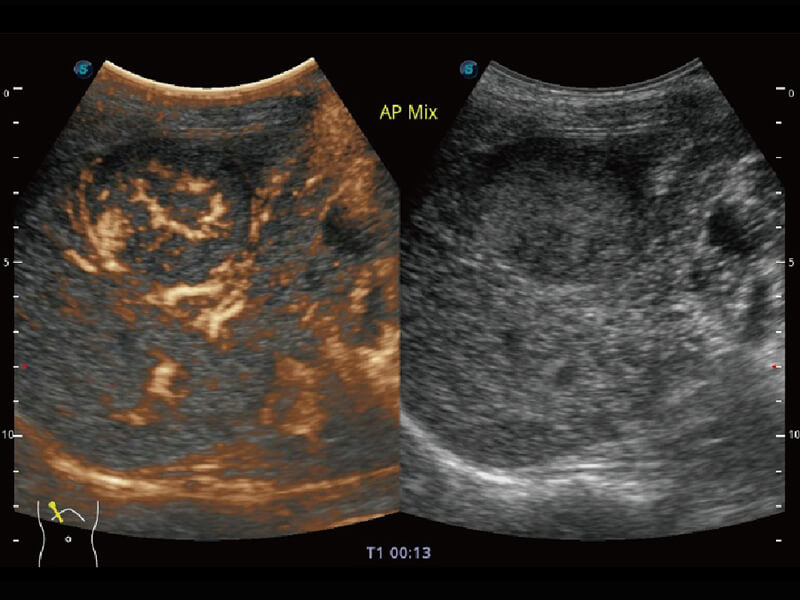

S60探头工艺,从前端信号处理每一个环节采集无损声学数据,真实还原组织原貌,再现解剖细节。

超宽频带技术,为容积成像带来优质的二维图像基础,为您呈现丰富的结构细节,栩栩如生地展示宝宝的宫内形态以及各种组织的立体结构。